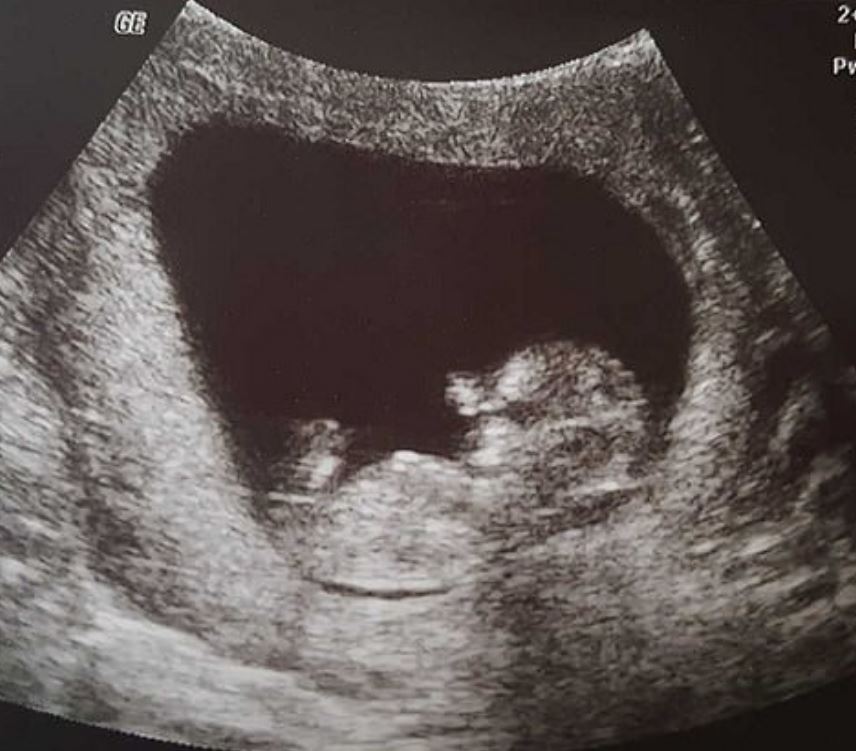

▼英國《每日郵報》報導,40歲的Sharran失去了腹中14週大的嬰兒Miran。醫生發現嬰兒在子宮內失去心跳,沒有辦法之下只能夠透過手術拿出肚子裡的嬰兒。

▼醫療「廢棄物」,這個詞讓Sharran聽了很震怒,直接在社群網站說:「即使我的嬰兒不在了,我卻可以擁他入懷,可以感受到愛,結局雖然不如想像,但是我依然很感激。」Sharran的孩子已經長出的手、腳、耳朵、舌頭,她直接就拒絕了讓醫院把自己的嬰兒當廢棄物處理掉。

▼她把照片上傳勸導那些要拿掉寶寶的媽媽,她很諒解或許很多人有自己的理由必須這麼做,但是她希望這些照片能夠讓更多人真的做之前,仔細再思考。是真的沒能力還是不想去付出努力?是真的不要還是只是一時的衝動?